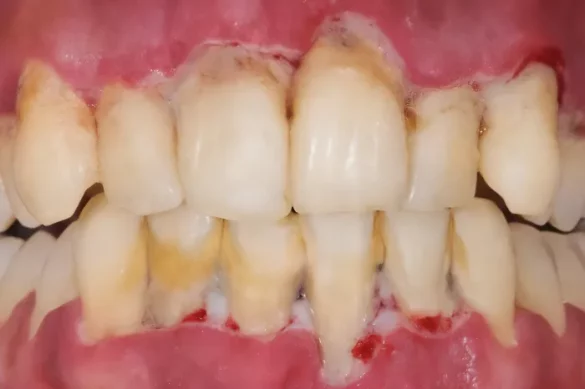

The most distinguishing feature of necrotizing periodontal disease is tissue necrosis. Patients typically experience intense gum pain, spontaneous bleeding, and rapid onset of symptoms. Other common signs include:

- swollen and ulcerated gums with a greyish pseudomembrane (a protein and white blood cell layer over dead tissue)

- Crater-like or “punched-out” appearance of the gums

Loss of gum attachment and the exposure of tooth roots or bone can occur quickly. Deep periodontal pockets are rare since the rapid tissue destruction does not allow time for typical pocket formation seen in other gum diseases.